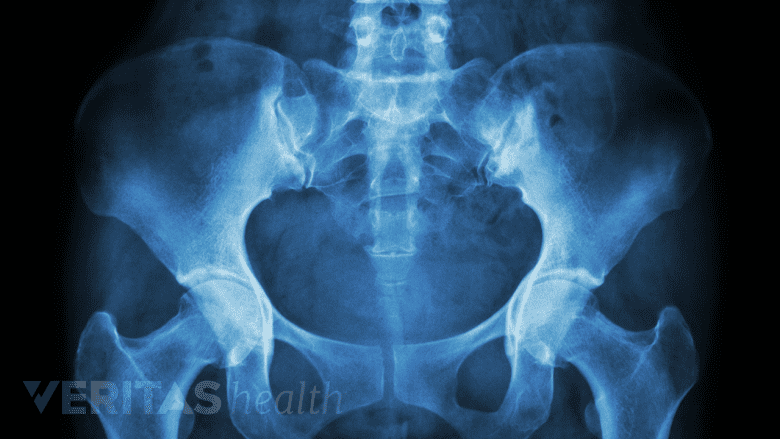

Analyzing the spinous processes of the lower back vertebrae helps identify spondylolisthesis.

X-ray images may help in the diagnosis of spondylolysis.

An anterior (front), posterior (back), and lateral (side) x-ray is used to confirm the diagnosis. An oblique view x-ray helps determine if the spondylolysis is one-sided or has occurred on both sides.